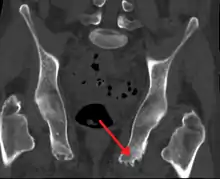

| Enthesopathy of the pelvis likely due to ankylosing spondylitis | |